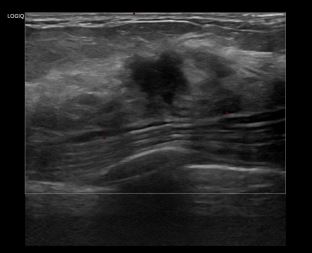

상기환자는 좌측유방 만져지는 멍우리로  내원하신 60대 초반 여성분으로 의심스러운 좌측 혹 조직검사 시행해 유방암 진단되었습니다.